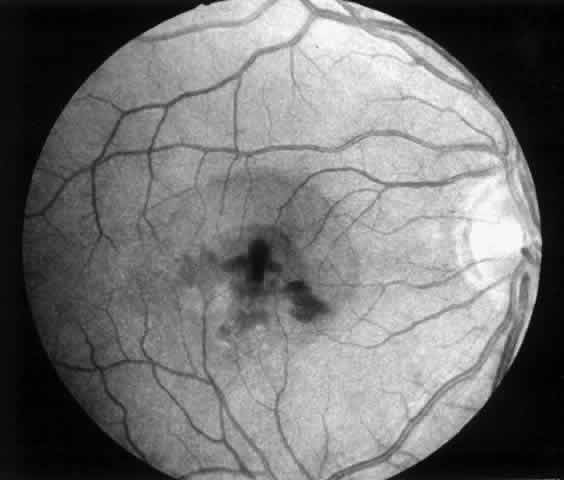

3. A 39-year-old patient with POHS developed a recurrent choroidal neovascular membrane involving the fovea with a decrease in vision to 20/100 (6/30) (Fig. 11). He underwent surgical excision but laser was not applied to the retinotomy site at the conclusion of the case. One month after surgery his vision improved to 20/30 (6/9) and the retinotomy was not noticeable (Fig. 12).

Fig. 11. Preoperative photograph of a 39-year-old patient with presumed ocular histoplasmosis syndrome (case 3). Visual acuity is 20/100 (6/30).